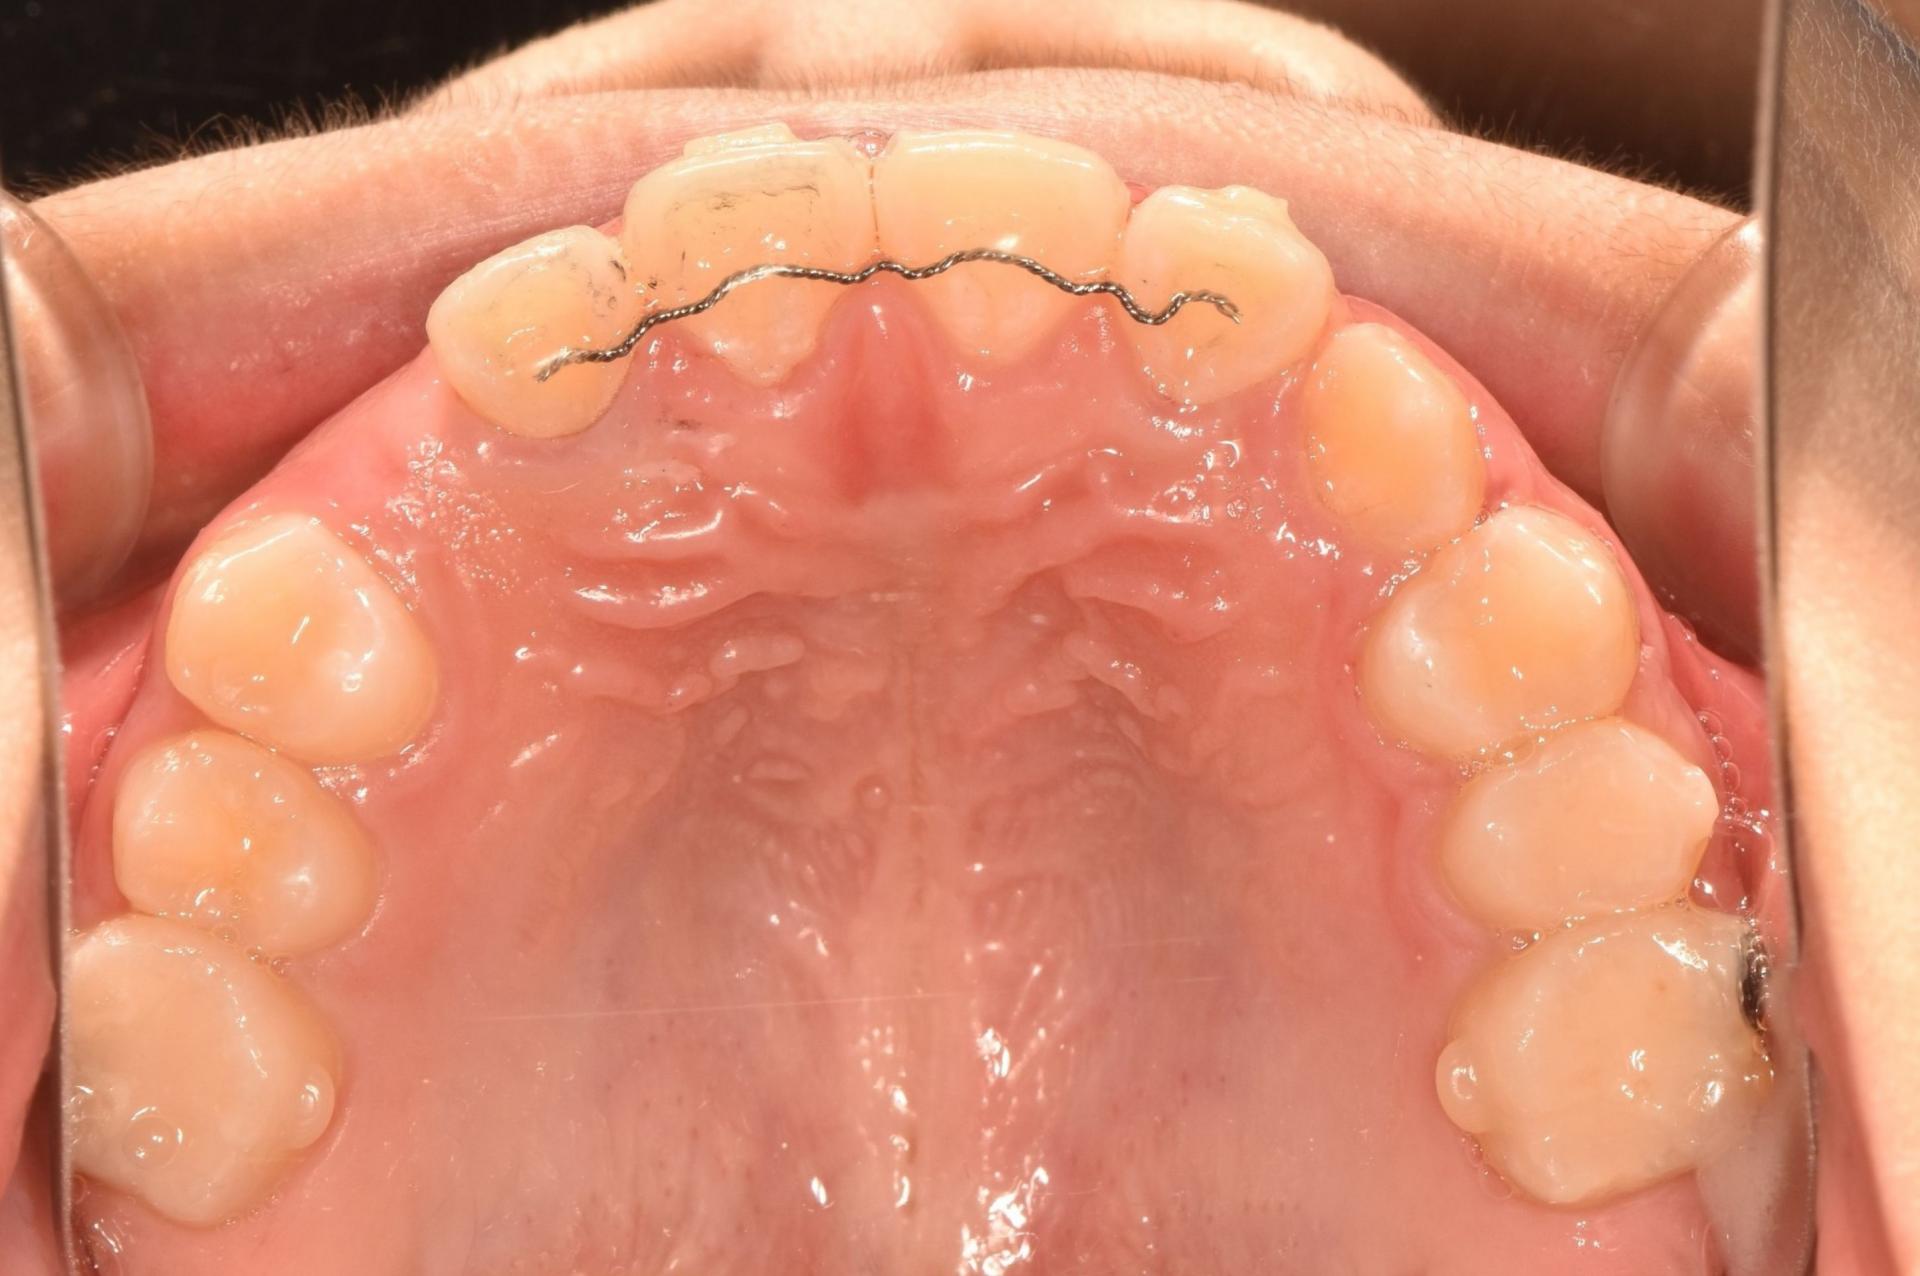

치료 전 구강 내 사진입니다 .

앞니가 벌어져 있고, 치아가 나올 공간이 부족합니다. 앞니끼리 서로 부딪히고 있네요.